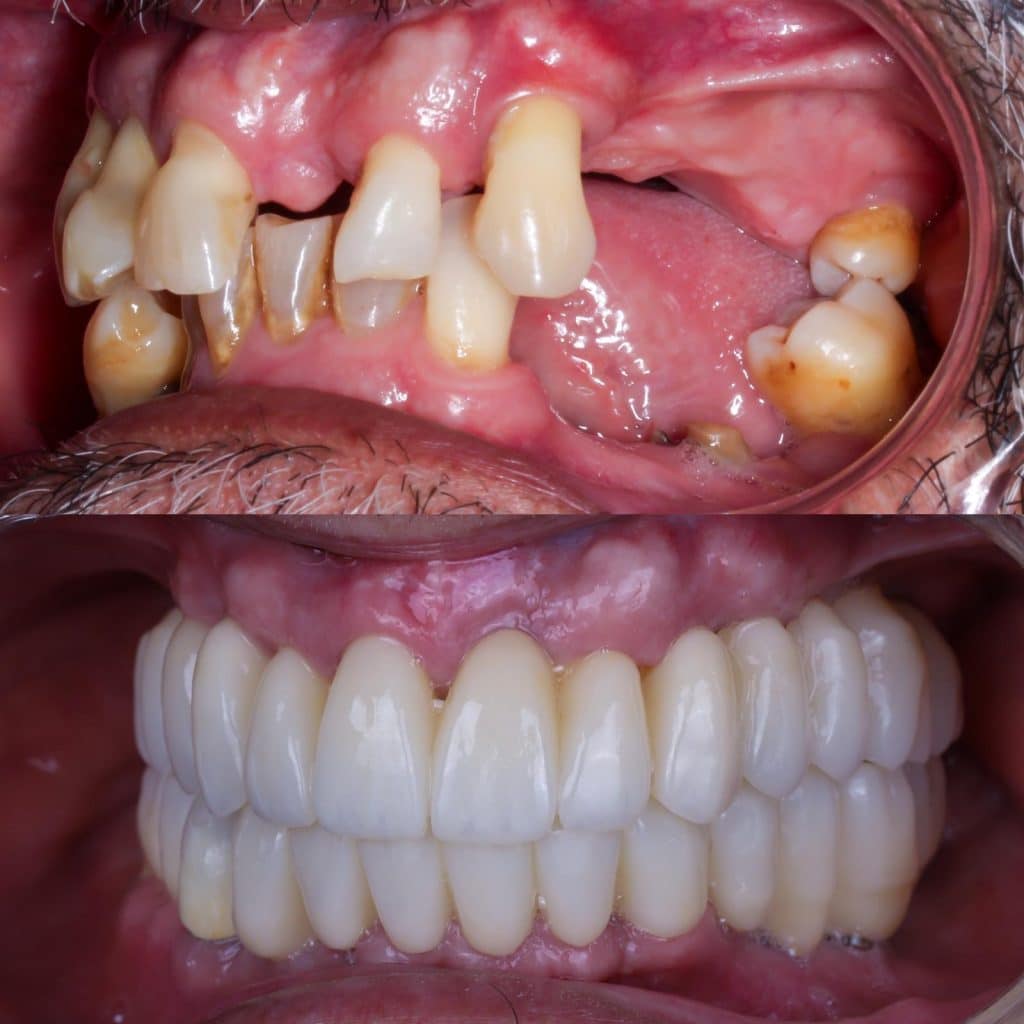

Mas abajo, se puede observar una foto de antes y después de uno de nuestros pacientes con caso de falta de hueso dental severa.

En este caso podemos ver el caso de uno de nuestros pacientes que no tenía hueso dental. Las opiniones de nuestros pacientes son muy positivas.